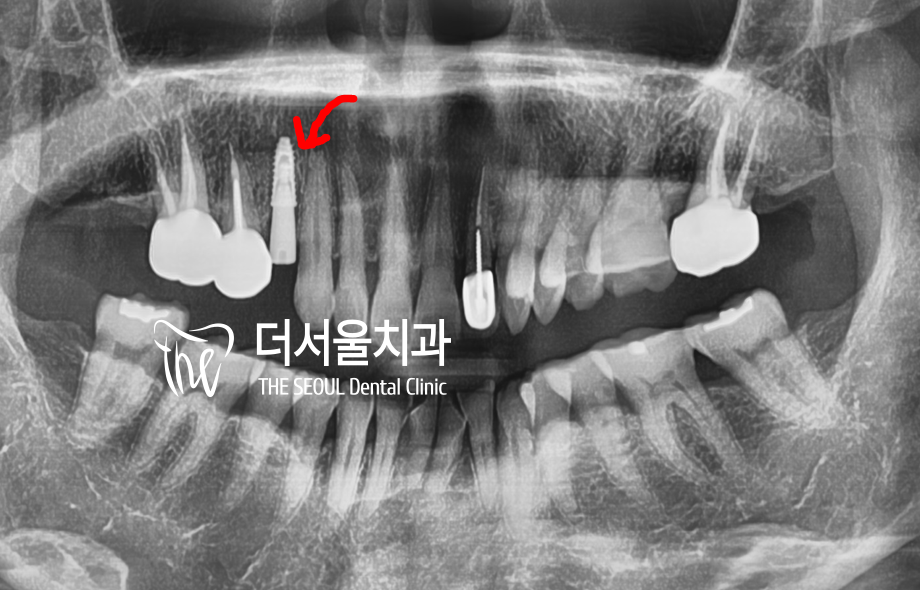

안녕하십니까 박현준 원장입니다. 내가 윗니가 빠져서 임플란트를 해야되는데 임플란트를 심을 곳에 뼈가 얇다? 그러면 90% 이상은 상악동 거상술 이라는 sinus